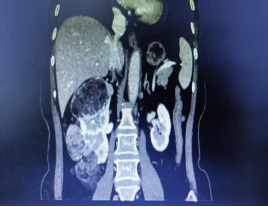

年近6旬的张女士(化名),近期在常规体检中发现右肾存在占位性病变,进一步检查后确诊为右肾多发肿瘤:最小直径约1cm,最大直径约8cm!尽管术前检查考虑良性可能,但由于患者肾脏肿瘤多发,保肾难度大,且对侧肾功能良好,术前检查无禁忌症,医生最终为她实施了全麻下腹腔镜右肾切除手术,张女士(化名)遗憾地失去一颗宝贵的肾脏。

术前影像